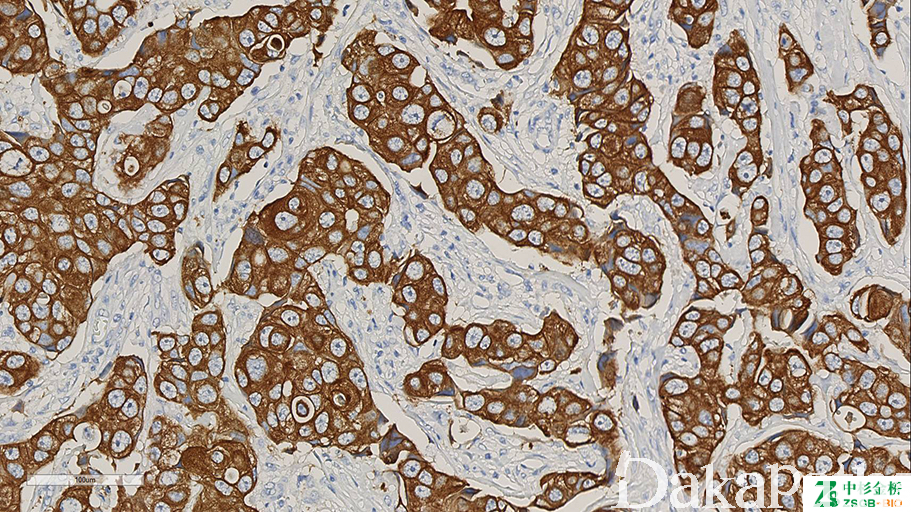

细胞角蛋白,能识别所有已知的碱性(II 型)细胞角蛋白。

信号定位: 胞质

肿瘤上皮性分化的标记之一。